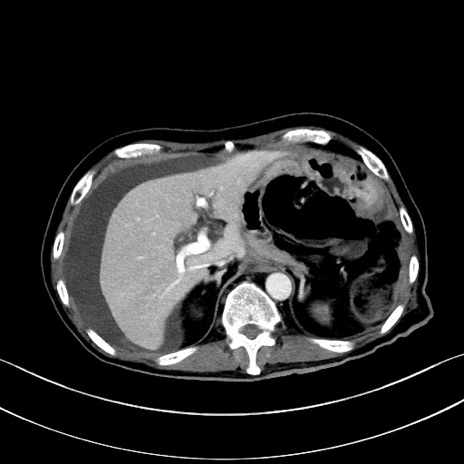

症例28(横断像)

【症例】60歳代男性

【主訴】嘔吐

【現病歴】胃癌にて胃全摘後。食思不振が悪化し、夜中に嘔吐することがある。

【既往歴】胃癌、胃全摘、脾摘、胆摘後

【データ】WBC 5900、CRP 10.56